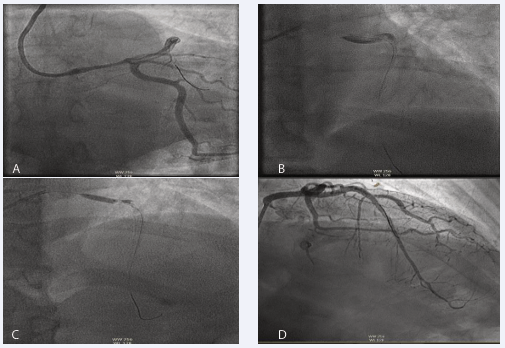

A 51-year-old patient first presented to the cardiology department in October 2019 with acute onset chest pain. Primary PCI pathway was activated due to her anterolateral ST elevation on 12-lead ECG. Notably, her cardiovascular risk factors included only smoking and raised BMI. Examination revealed a diaphoretic, tachycardic patient, but was otherwise unremarkable. Blood pressure was maintained. Coronary angiography showed an occlusion in the mid-left anterior descending (LAD) artery and a spontaneous coronary artery dissection (SCAD) not linked to coronary artery disease. She was treated percutaneously with drug eluding stents (DES), discharged, and remained asymptomatic during follow-up visits (Figure 1 and Table 1).

Figure 1: Coronary angiography from initial presentation in 2019. (A) Anteroposterior Cranial view. Arrow 1 highlights SCAD in mid part of left anterior descending after the first diagonal branch, arrow 2 demonstrates SCAD in distal marginal branch. (B) Right anterior oblique cranial view post PCI to mid left anterior descending (LAD) artery following deployment of 2 drug eluting stents (DES)